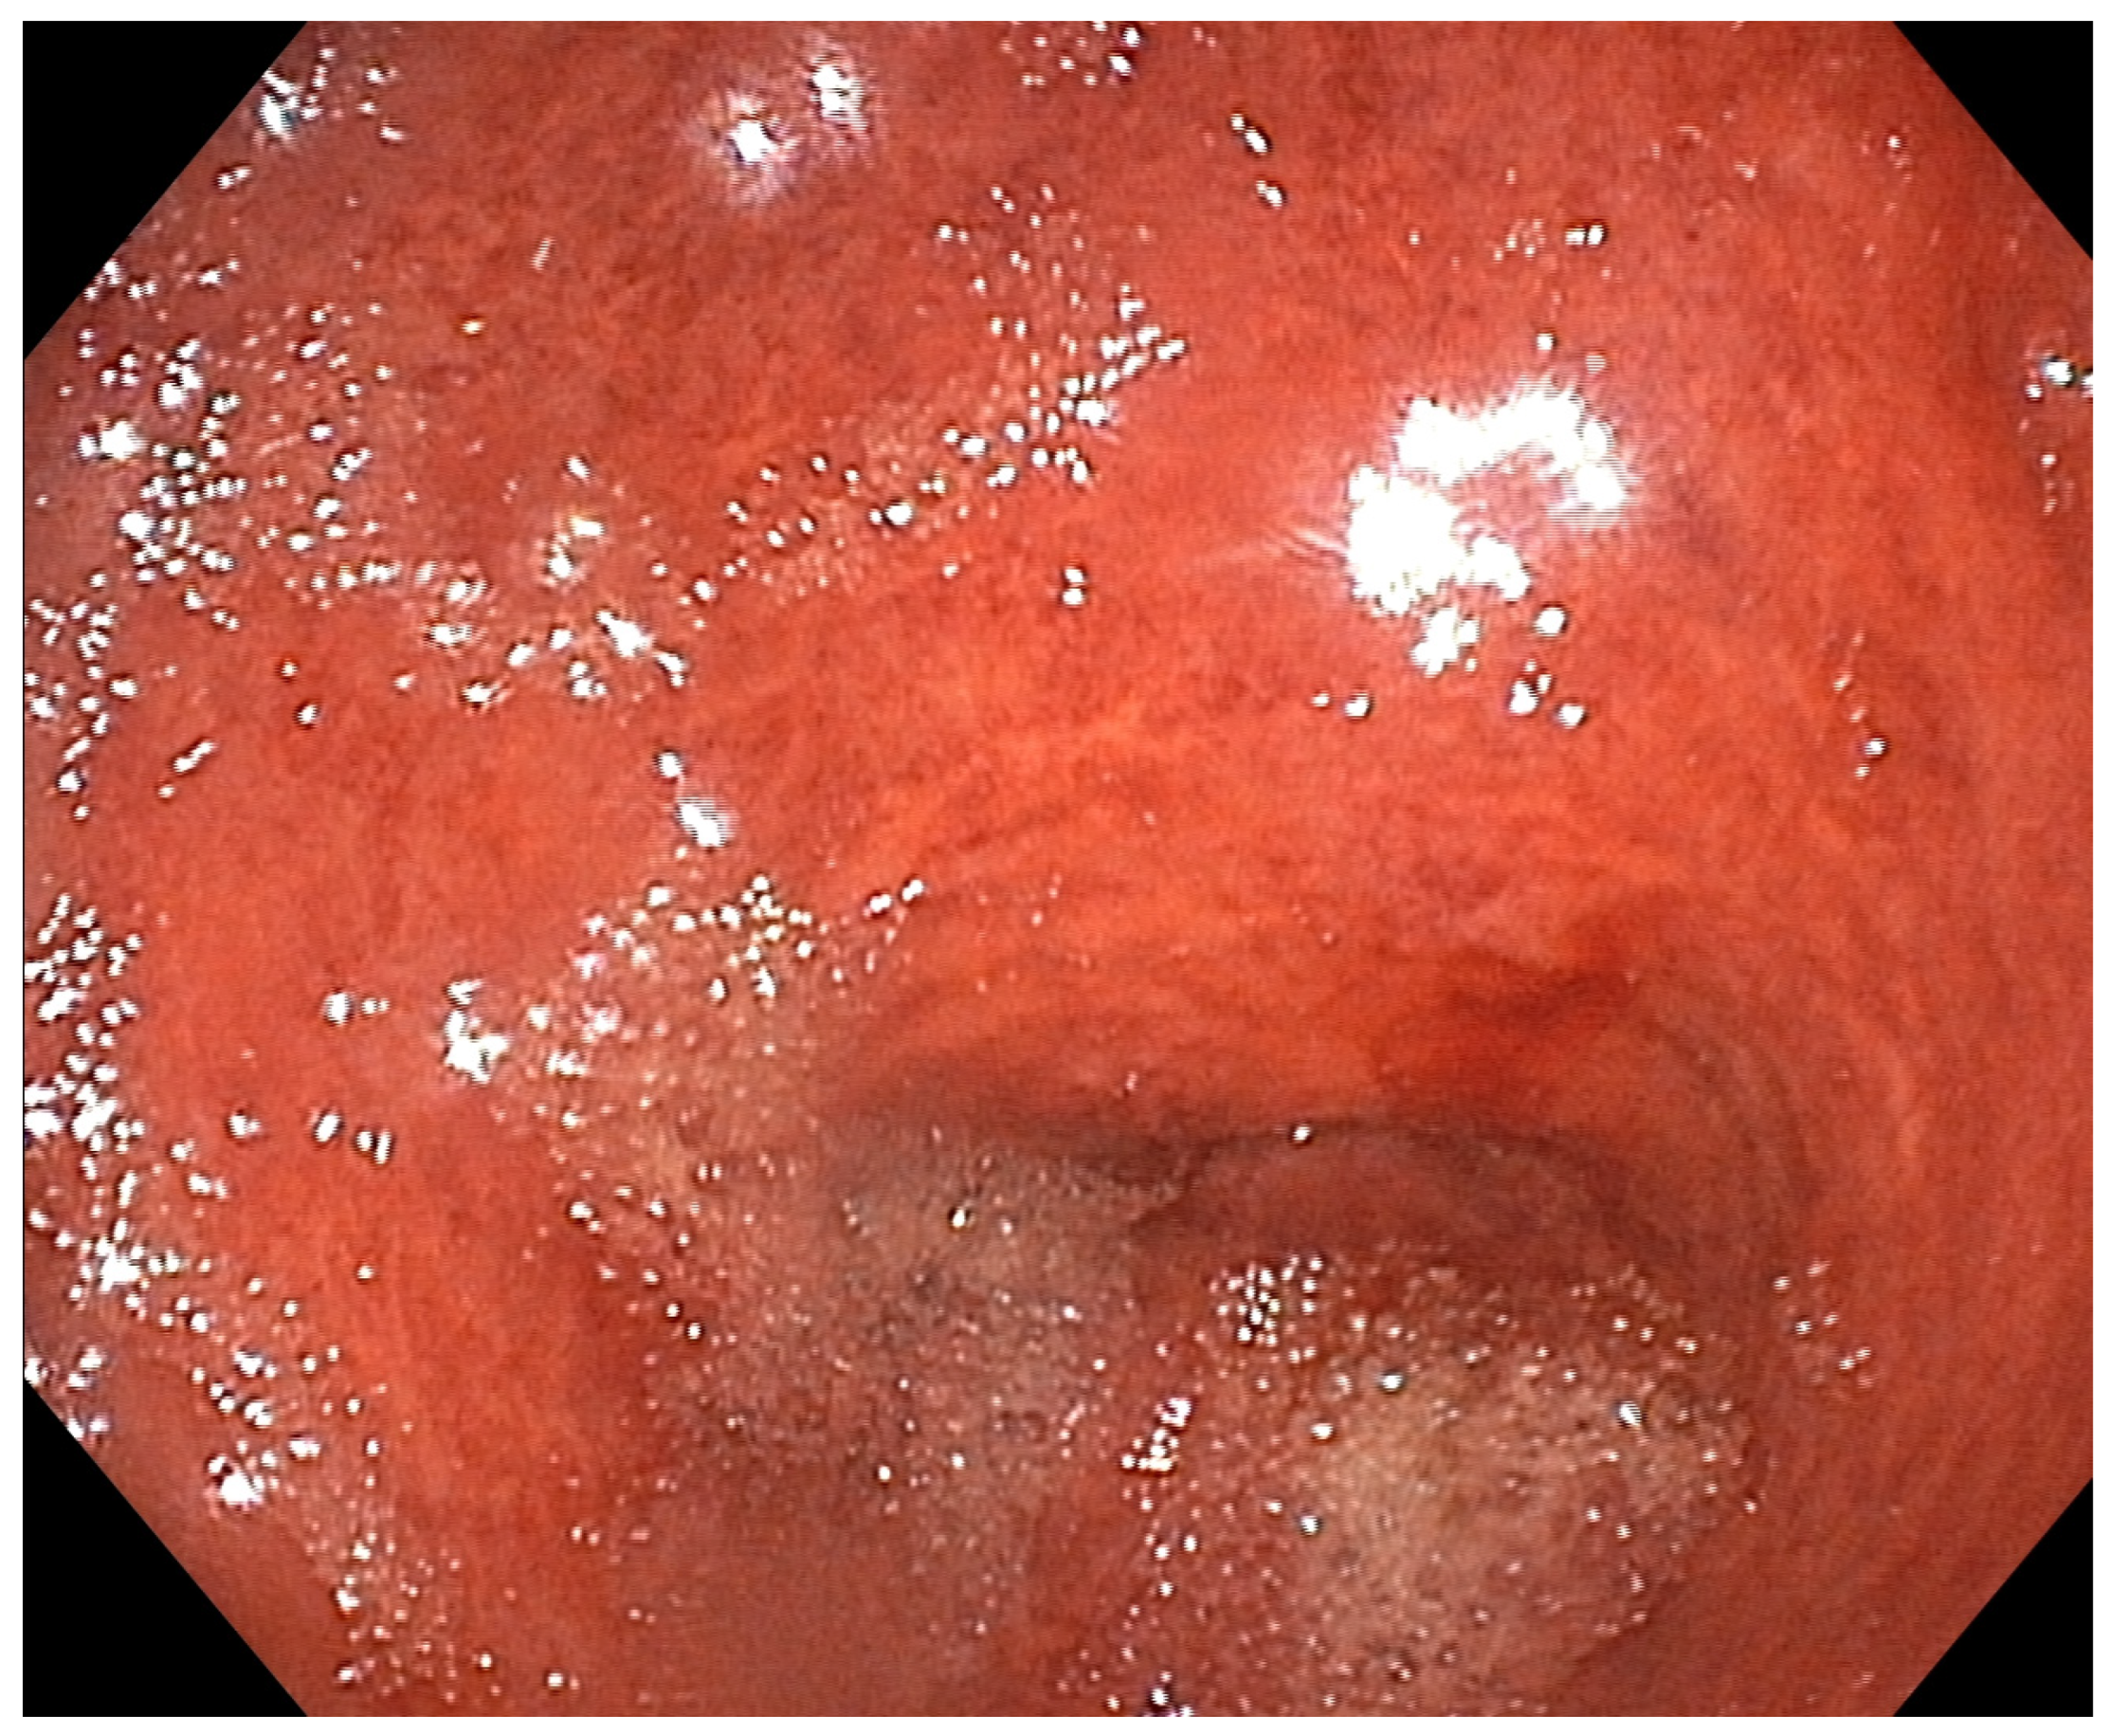

Hepatic Portal Venous Gas (HPVG) after Ingestion of Chlorine Bleach: A Transient Phenomenon

Arico, F.M.; Buemi, F.; Pitrone, P.; Giardina, C.; Trimarchi, R.; Borruto, F.; Doria, S.; Turiaco, C.; Caloggero, S. Hepatic Portal Venous Gas (HPVG) after Ingestion of Chlorine Bleach: A Transient Phenomenon. Diagnostics 2023, 13, 3615. https://doi.org/10.3390/diagnostics13243615